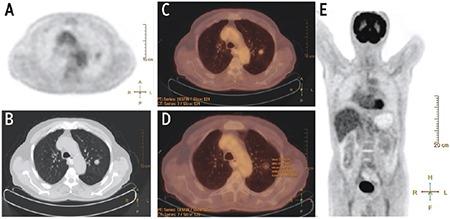

SPN diameter, SUV, metabolic tumor volume (MTV), total lesion glycolysis (TLG), and density were significantly higher in the malignant group. SUV, MTV, TLG increased in direct proportion to the diameter. There was no a significant difference between GGO, PS, and solid nodules in terms of SUV values. MTV and TLG values increased in parallel with the density of the nodules, but this increase was only significant in the malignant group. There was a significant difference between SPNs <2 cm and SPNs ≥2 cm in terms of MTV, while there was no difference in terms of SUV. The cut-off value determined by the ROC curve was found to be 4.39 for SUV, 7.33 mL for MTV and 31.88 g for TLG. The cut-off values for SUV of solid and subsolid nodules were close to each other, but cut-off values for MTV and TLG were higher in solid nodules.

SUV, MTV, and TLG are affected by diameter and attenuation. We suggest using different MTV and TLG cut-off values for solid and subsolid nodules, but we suggest using same SUV values. MTV can be a more reliable parameter than SUV in prediction of malignancy in smaller nodules.